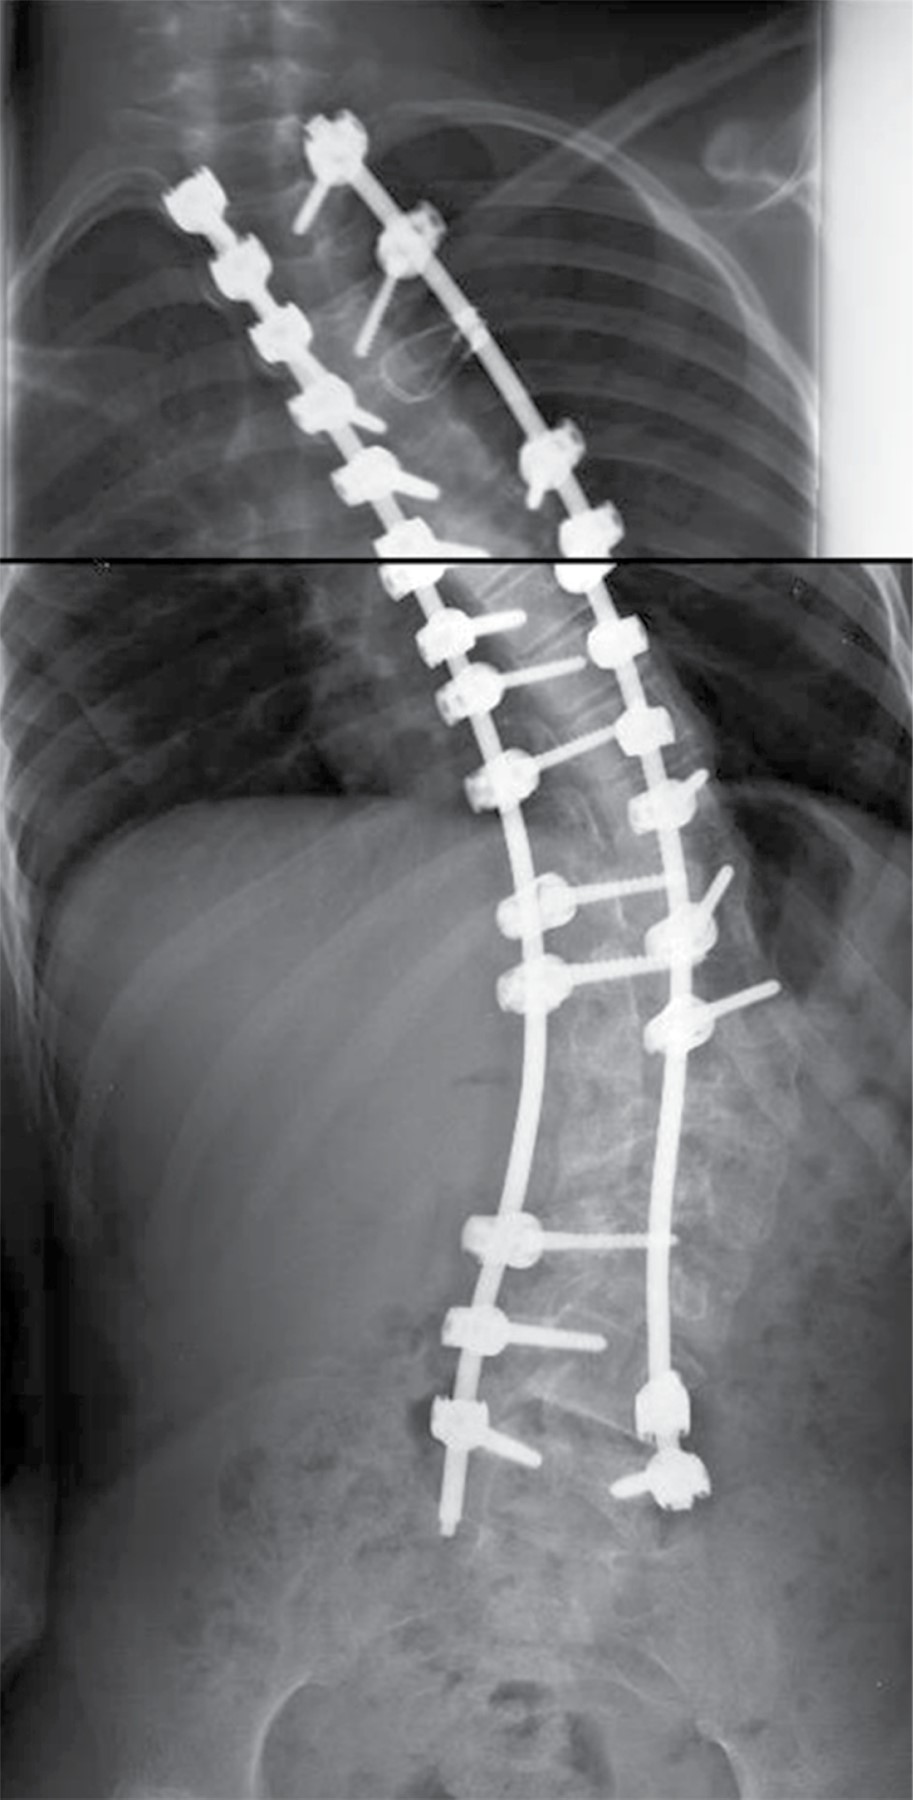

Introduction: Scoliosis is a complex deformity that affects all three planes of the axis of the spine. The association between neuromuscular pathology and vertebral alignment was initially described in 1960. Neuromuscular pathology is progressive and results in postural abnormalities. Surgical goals in patients with neuromuscular deformity include anatomical correction for sedation and ambulation, as well as functional improvement. The gold standard of treatment is by posterior approach with transpedicular screws. The "hands-free" technique saves surgical time, decreases radiation by reducing the use of fluoroscopy. The advent of 3D printing technology allows precise study of the anatomical area and detail of the deformity in its three planes. This model can be sterilized for transoperative guidance. A 13-year-old female patient who develops thoracolumbar neuromuscular scoliosis secondary to spastic cerebral palsy (CP), with previous instrumentation T11-L3 of which he develops severe proximal curve. After the segmentation of the three-dimensional model, pedicle violation greater than 2 mm towards bilateral medullary canal was detected in the pedicles of L1 and L2 of previous instrumentation, pedicle dysplasia and the morphological characteristics of the pedicles were observed. Three-dimensional planning and the use of surgical guides represent a tool for surgical planning, especially in severe cases and with pedicle dysplasia. It helps as a surgical guide for the placement of hands-free transpedicular screws with possible reduction of radiation and anesthetic time.

Figure 5

Figure 6